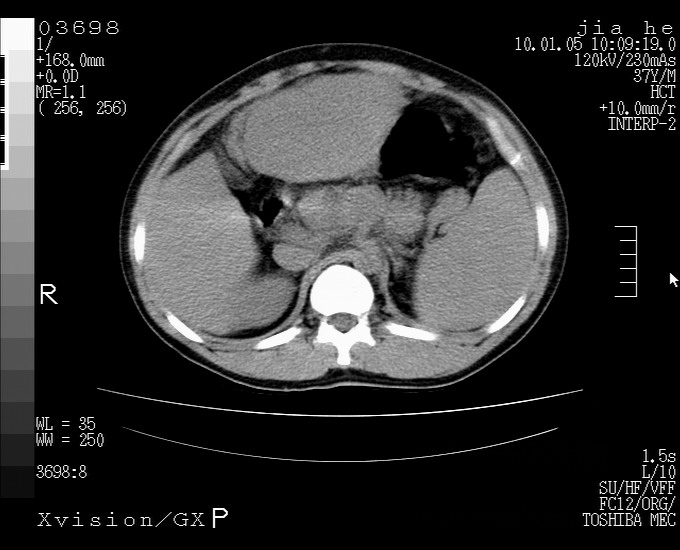

标题: CT23988:男,40岁,B超提示腹部肿物,请各位老师给看看。 [打印本页]

标题: CT23988:男,40岁,B超提示腹部肿物,请各位老师给看看。

左叶够大的,且与胰腺欠清晰,请增强扫描

肝左叶增大,建议增强扫描。

1.该患者有腹部手术史

2.脾大,肠系膜密度增高,有多发索条影,胰腺边缘毛糙,腹膜增厚,推测有肝硬化,门脉高压,腹膜炎和/或胰腺炎

3.肝左叶巨大站位,并腹腔淋巴结肿大,肝癌或肝间叶来源恶性肿瘤,也不排除大网膜间质瘤侵及肝左叶

建议:增强或磁共振